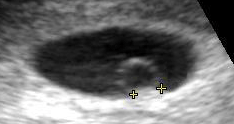

![]() Contents in the cavity of the uterus seen at approximately 5 weeks of gestational age by obstetric ultrasonography. | |

On obstetric ultrasound, the gestational sac is a dark ("anechoic") space surrounded by a white ("hyperechoic") rim.

Gestational sacs can be identified via ultrasound and are generally identified by the following 4 characteristics:

- The sac has a round or elliptical shape in longitudinal and transverse views

- it is surrounded by a white echogenic rim ("choriodecidual reaction")

- The sac is located in the uterine fundus

- The sac is not implanted on the midline, but eccentrically (to one side of the uterine cavity line).